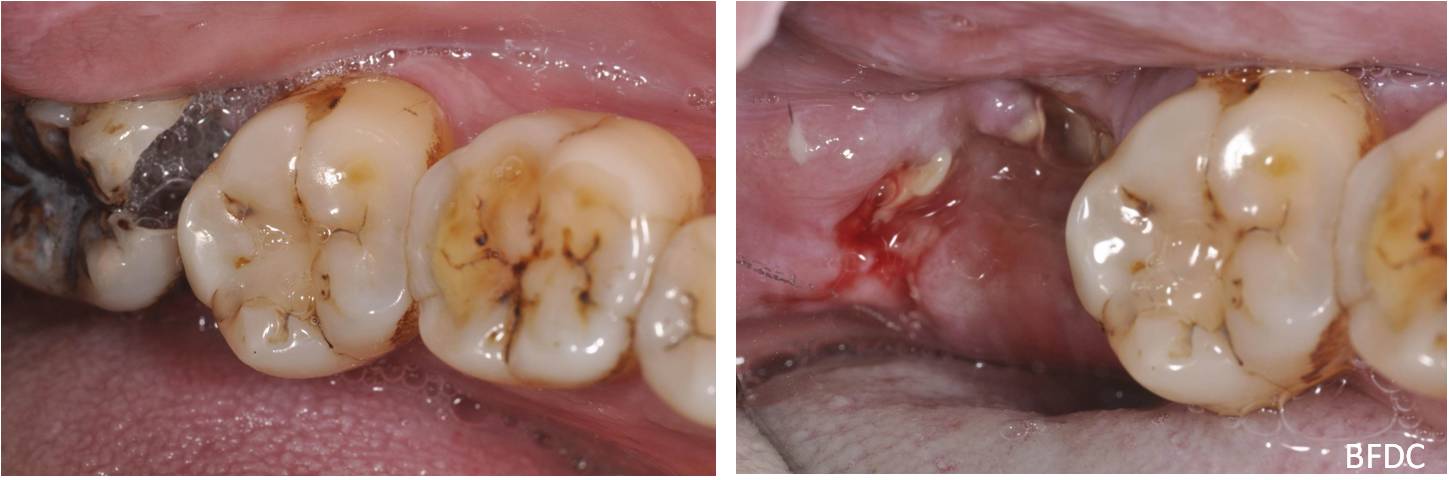

治療前,阻生齒塞食物,清潔不易,深度蛀牙

治療前,深度蛀牙

阻生齒外科手術拔除,補骨膠原

術前、術後比較